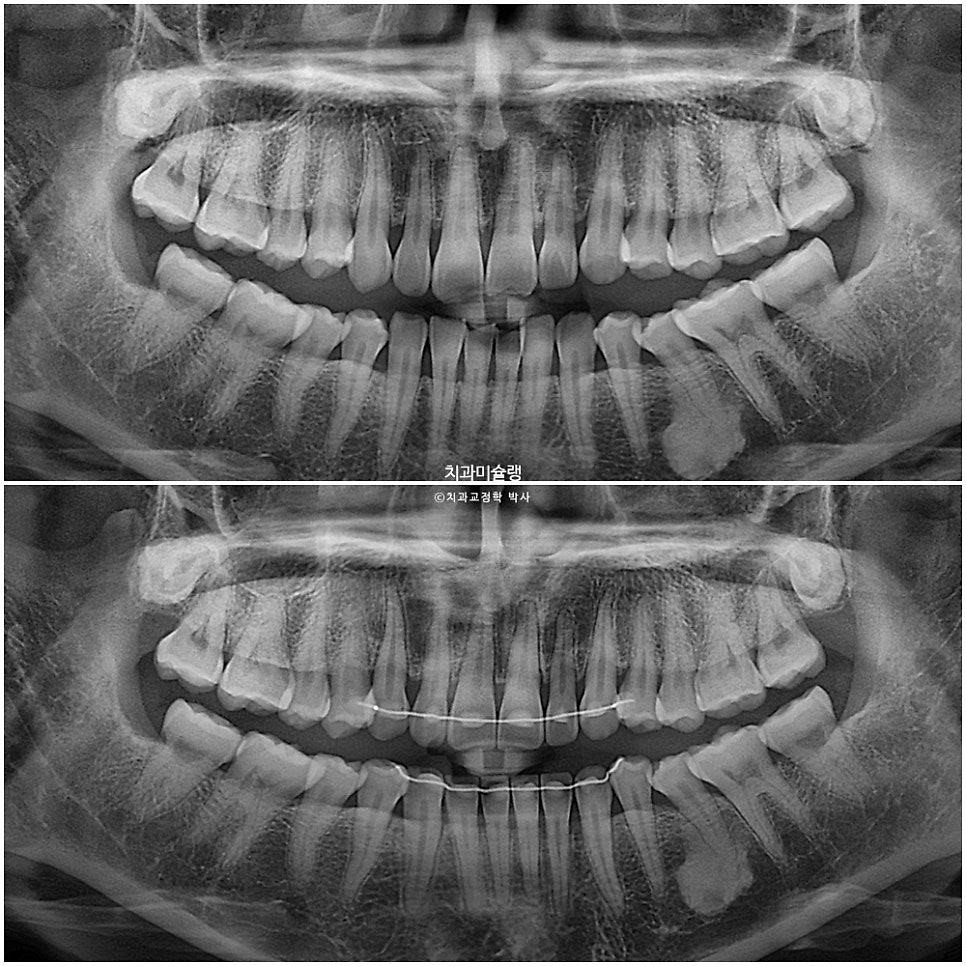

엑스레이상 치근흡수는 없으며 치근평행도는 양호합니다.

작은어금니를 빼지 않은 비발치 교정에서는 철사 고정식 유지장치를 송곳니에서 송곳니까지 6개만 붙입니다.

하지만 앞니를 함입시켜 과개교합을 개선했기 때문에, 재발방지를 위해 유지장치를 작은어금니까지 좌우 1개씩 더 연장시킵니다.